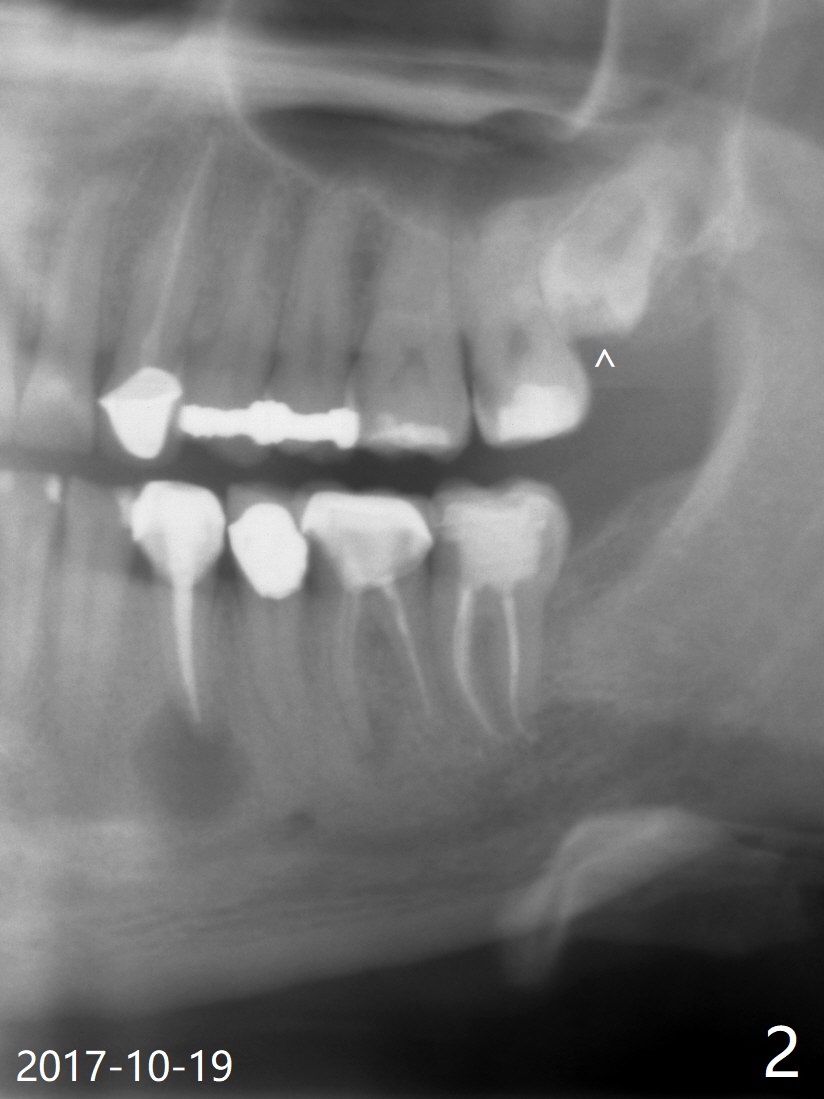

A 37-year-old man complains of food impaction between #14 and 15, which may be related to mesioangular impaction of #16 (Fig.1 ^ (* a supernumerary premolar; #20 asymptomatic after RCT retreatment)). When the third tooth is removed, it is smaller than expected. Intraop X-ray reveals a normal sized 3rd molar in situ (Fig.2 ^). Therefore the microdontia removed is a supernumerary tooth. The tooth #16 is then extracted. The diastema appears to persist 2 years 7 months postop (Fig.3), although gingival swelling and pain reduces. There is a significant increase in PARL at #20, supported by 2 PAs (Fig.4,5). The tooth has no mobility with normal periodontal pockets. There is no paresthesia of the lower left lip.